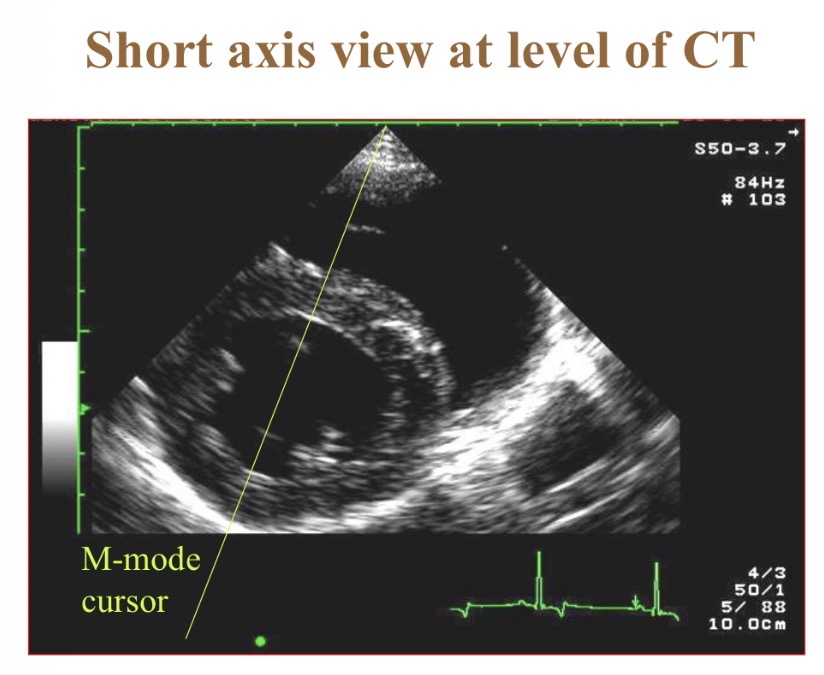

Types of views - B

Short axis view

Levels of short axis views - a

Papillary

Levels of short axis views - B

Mitral

Levels of short axis views - C

Aortic

Levels of short axis views - D

LV

What does M-mode echocardiography show

Wall thickness/position over time/ ECG